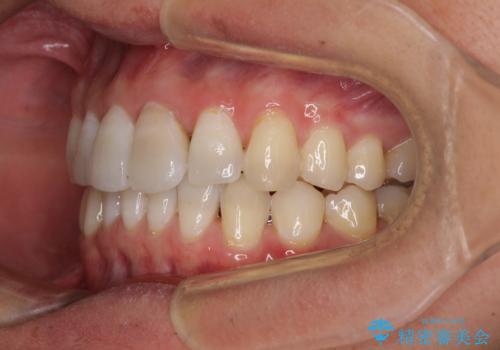

前歯のデコボコを治したい インビザラインによる矯正治療

- 前歯のデコボコを治したいとのことで来院された患者様です。

上下顎ともに歯列全体の後方移動とIPR(歯と歯の間を削る)によってデコボコが解消するように設計し、インビザラインにより治療を行うこととしました。

矯正治療後、前歯の形と色が気になるとのことでしたが、大分前に失活している(神経が取り除かれている)歯であり、その影響で変色しているため、オールセラミッククラウンによる補綴治療をおすすめいたしました。